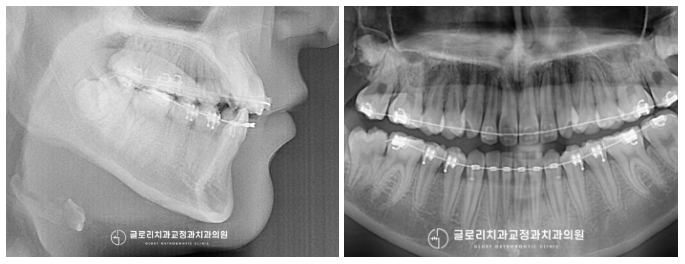

치료 중간중간 방사선 촬영을 진행하여

치근 흡수는 나타나진 않는지,

눈에 띄지 않는 곳에 충치가 생긴 건 아닌지,

원하는 방향으로 잘 움직이고 있는지

확인을 도와드렸죠^^